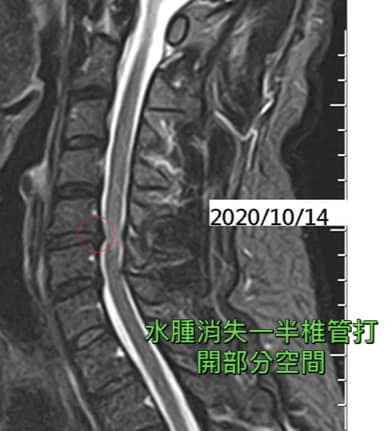

2020/10/14 MRI

(比較前後影像差異)

#術後對比水腫消失一半椎管打開一些

心得:這個是等待了快一年兩個月的醫案,從影像醫學來看有明顯的進步,但距離正常人還有一段空間,不過最重要的是患者的臨床症狀幾乎全部消失,永遠記得葉先生笑著跟我說!他從來沒想過他這輩子還能夠再度回到球場上打籃球,我們團隊非常的開心看到他重回球場